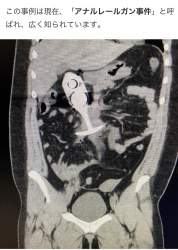

1770176734054.jpg-(30735 B)

30735 B

1770178125219.jpg-(128719 B)

128719 B

なぜ肛門に異物を入れてしまうのか